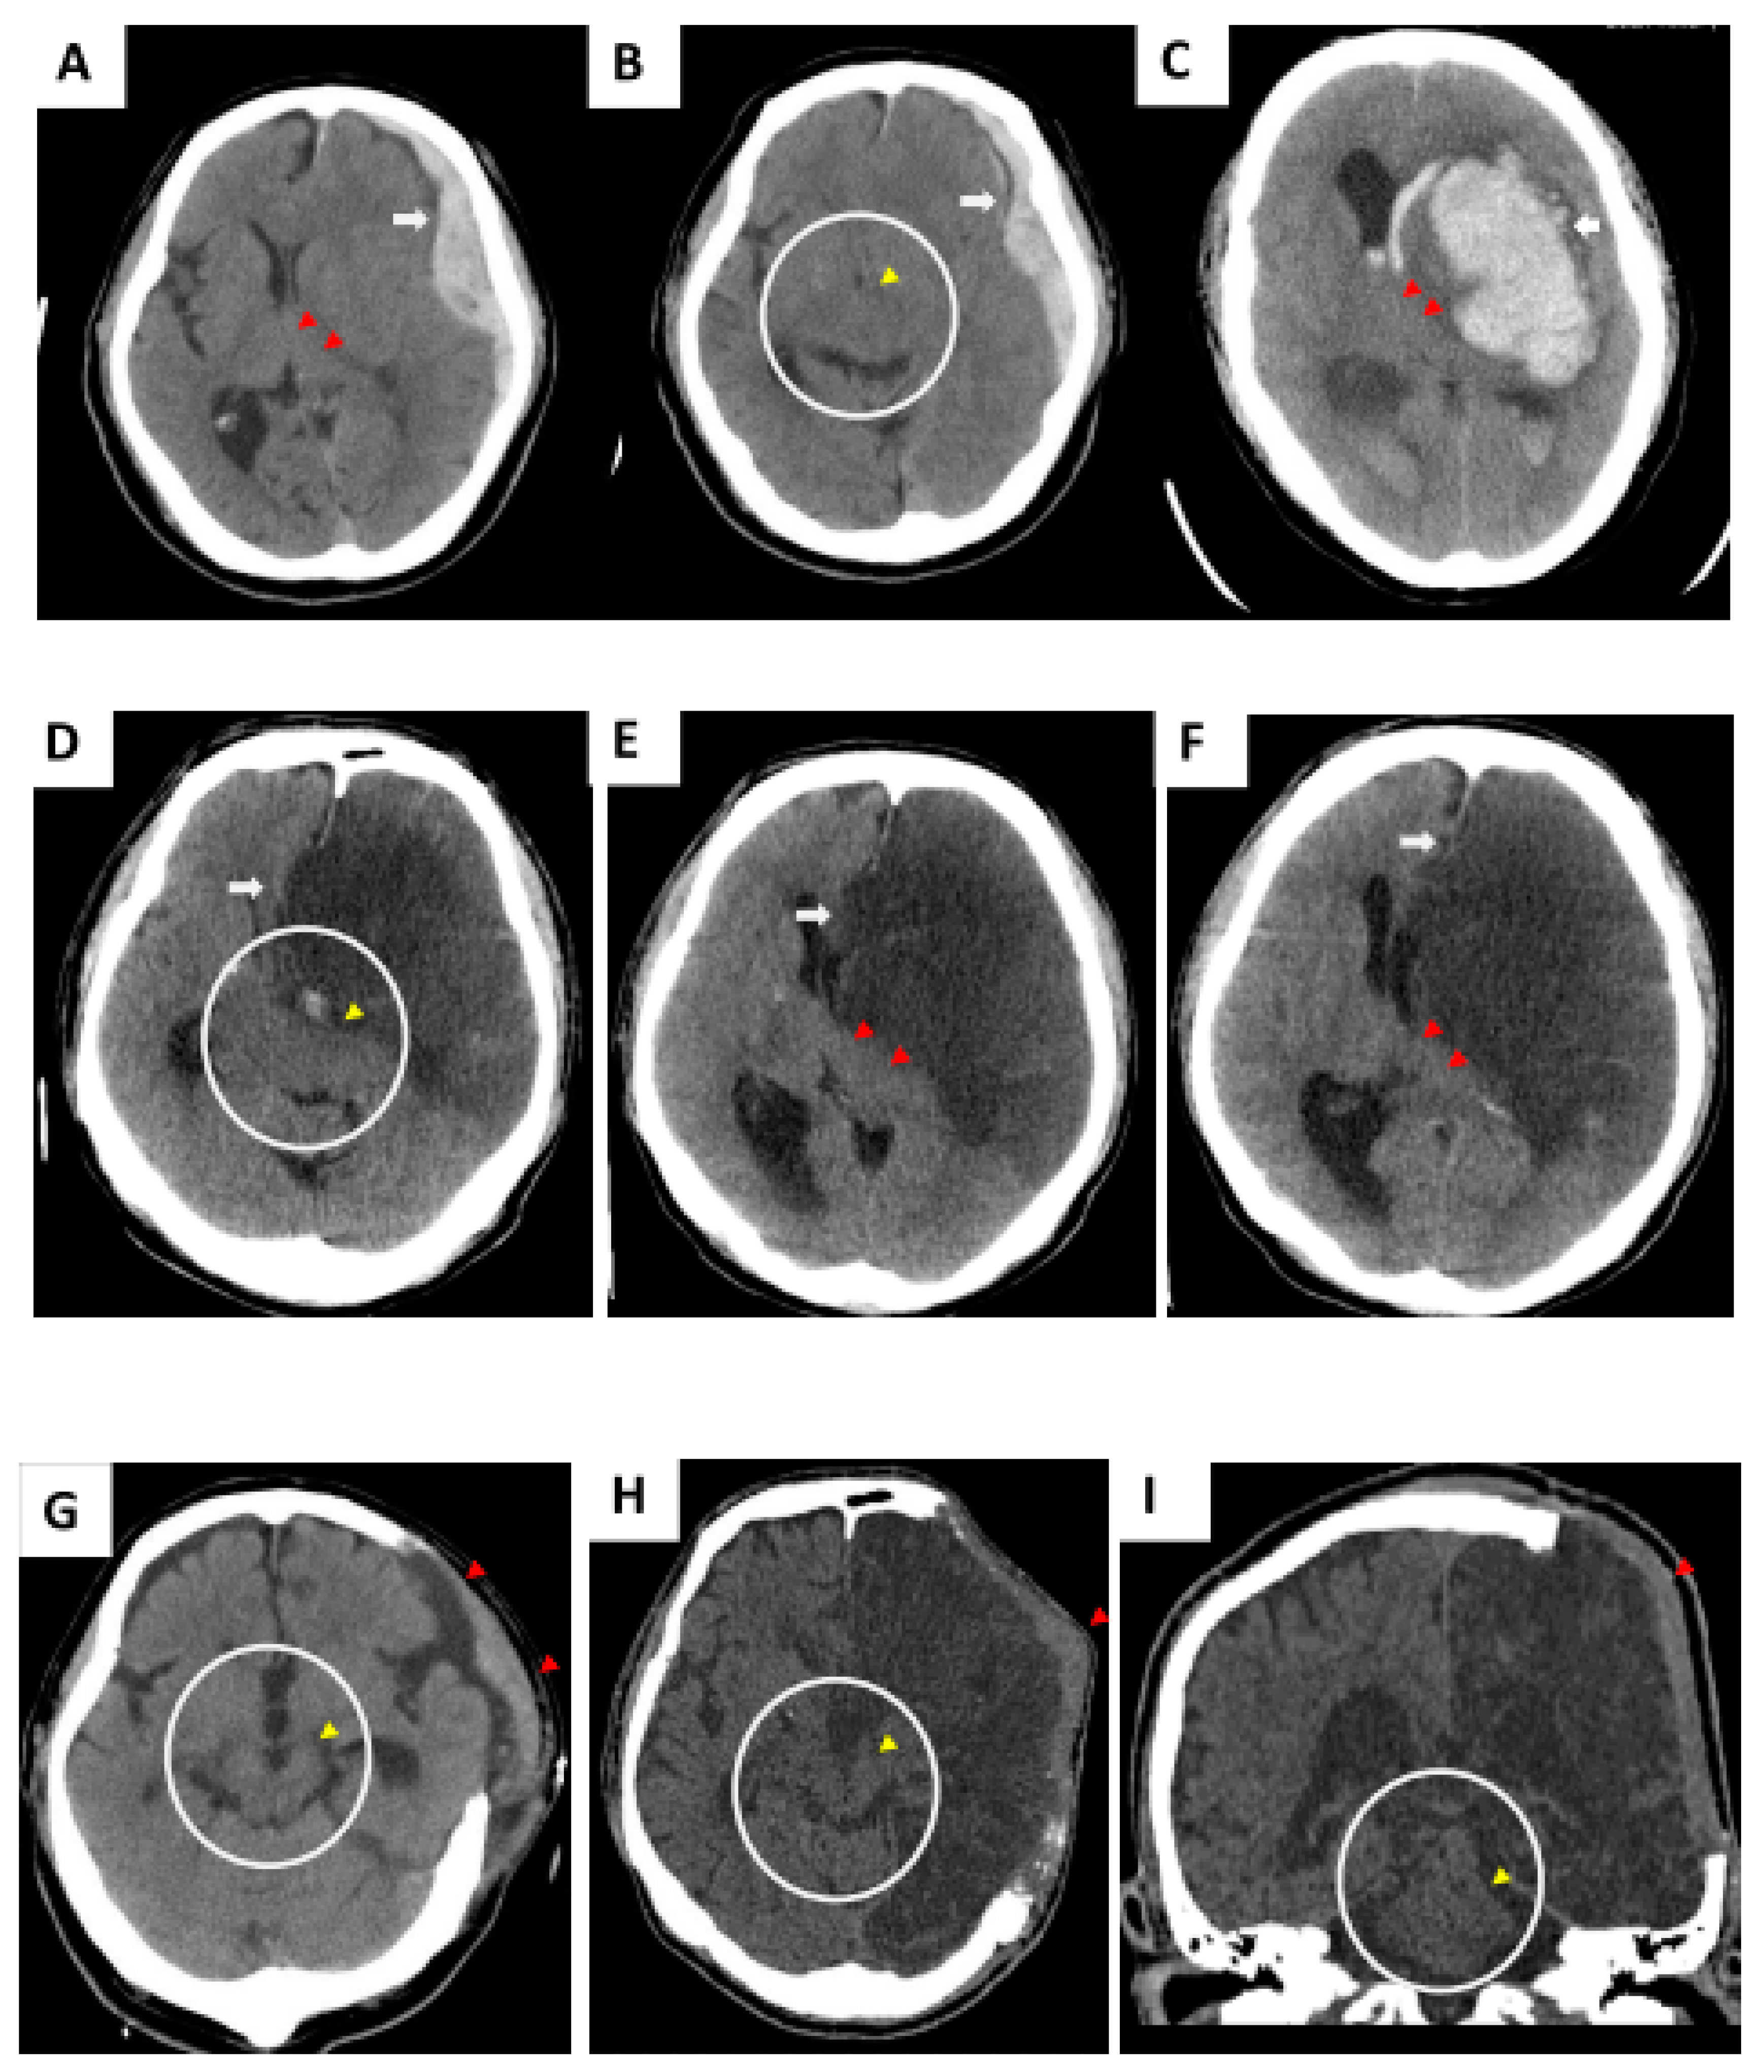

Decompressive craniectomy is frequently performed in cases of resistant intracranial hypertension secondary to several neurological conditions and is commonly followed by cranioplasty. Complications such as infection and hematomas after cranioplasty occur in roughly about a third of cases. Usually swelling happens quickly and is simple to treat with some combination of rest ice elevation medication or removal of excess fluid.